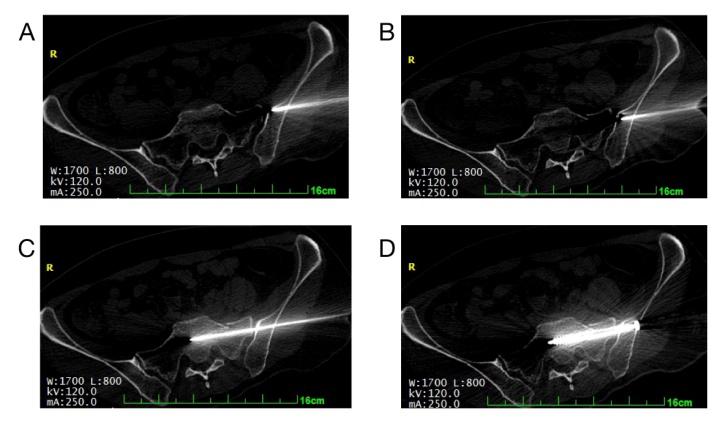

1.2 移动CT引导下骶髂关节螺钉的操作过程麻醉后。患侧臀部纵行安放3排定位针,移动CT下定位扫描,确定最佳横行扫描层数和纵行定位针以及进针角度。打开激光束和定位针交叉处即为最佳进针点。(图 1)消毒铺巾后,沿皮肤定位点用2.5克氏针刺入,参考扫描的角度方向直至髂骨外板,用榔头敲入1~2 cm,使其能稳定地固定在髂骨外板上。用无菌中单覆盖,然后在移动CT下扫描确认针的进入方向。若有偏移,参考其位置及角度置入另一根同等的克氏针,直至移动CT确认导针的位置准确。根据CT上测量深度后,在髂骨外板攻丝后,置入选定的7.3 mm或6.5 mm的空心拉力螺钉。(图 2)

| 图 2 移动CT术中的扫描图像 |